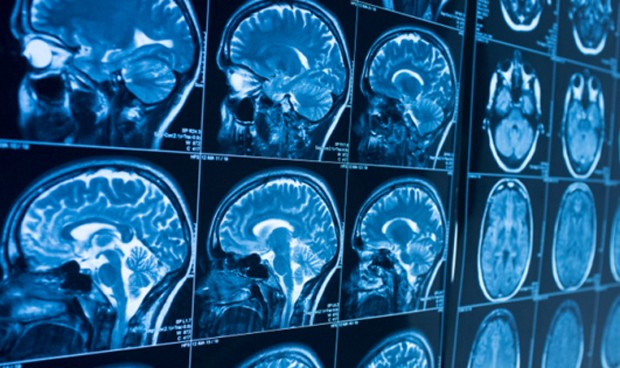

Investigadores de Estados Unidos han identificado, en un estudio multiinstitucional publicado en la revista Radiology, una alta frecuencia de síntomas neurológicos en pacientes con SARS-CoV-2, la enfermedad que provoca el nuevo coronavirus.

El propósito de este estudio actual ha sido describir los hallazgos de neuroimagen distintos del accidente cerebrovascular en pacientes con Covid-19 grave e informar del perfil clínico y biológico de estos pacientes.

Se incluyeron en el estudio pacientes con infección por Covid-19 y manifestaciones neurológicas que se sometieron a resonancia magnética cerebral del 23 de marzo al 27 de abril de 2020 en 16 centros franceses, incluidos 11 hospitales universitarios y cinco hospitales generales.

Entre los 37 pacientes incluidos, el 76 por ciento se asociaron con un patrón de neuroimagen, el 19 por ciento con dos patrones y el 5 por ciento mostraron tres patrones. Los hallazgos de resonancia magnética más frecuentes fueron: anormalidades de señal ubicadas en el lóbulo temporal medial en el 43 por ciento pacientes, lesiones hiperintensas multifocales de materia blanca no confluentes en Flair y secuencias de difusión, con realce variable, con lesiones hemorrágicas asociadas en el 30 por ciento de los pacientes y microhemorragias de sustancia blanca extensas y aisladas en el 24 por ciento de los pacientes.

Asimismo, el 54 por ciento tenían lesiones hemorrágicas intracerebrales y una presentación clínica más severa. "Se pudieron distinguir tres patrones neurorradiológicos principales, y la presencia de hemorragia se asoció con un peor estado clínico. Se detectó ARN del nuevo coronavirus en el líquido cefalorraquídeo en un solo paciente, y los mecanismos subyacentes de afectación cerebral siguen sin estar claros. Las imágenes y el seguimiento neurológico deben llevarse a cabo para evaluar el pronóstico de estos pacientes", han zanjado los investigadores.